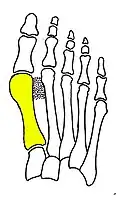

Syndesmosis procedure addresses specifically the two fundamental problems of metatarsus primus varus deformity that gives rise to the bunion deformity. They are leaning and instability of the first metatarsal bone . Syndesmosis procedure uprights the leaning first metatarsal bone with strong binding sutures between it and the second metatarsal bone (Fig. 2) and then also stabilizes it uniquely by creating a fibrous connecting bridge between these two bones (Fig. 3, 4). First metatarsal bone can be readily realigned because by definition of the metatarsus primus varus deformity its first metatarsal is abnormally loose and mobile.